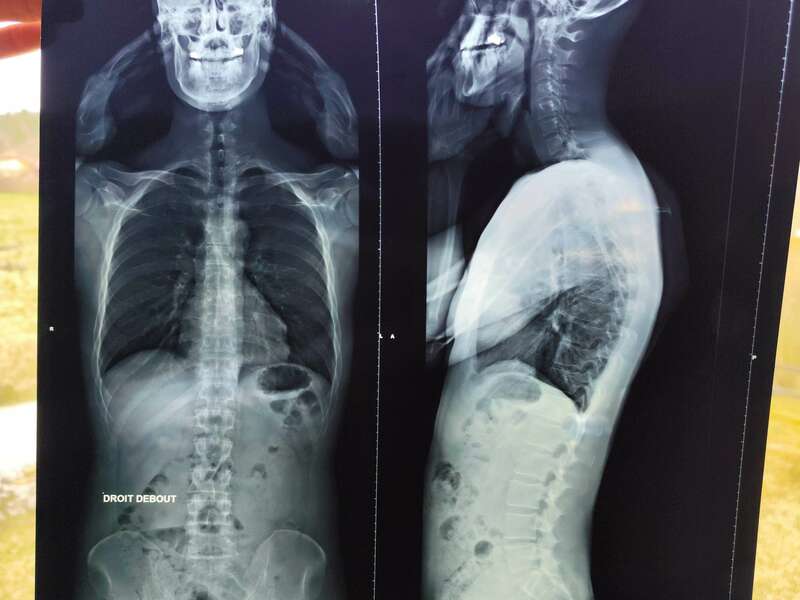

- En 2015, j’ai rechuté : une nouvelle hernie discale sur L5/S1, exactement comme celle que j’avais eue en 2007 ;

- Pendant plus de 10 ans, j’ai enchaîné lumbagos, sciatiques, hernies discales, arthrose et douleurs lombaires chroniques !

En 2015, une deuxième hernie discale m’a littéralement plié en deux…

Pendant plus d’un an, la douleur ne m’a quasiment pas lâché !